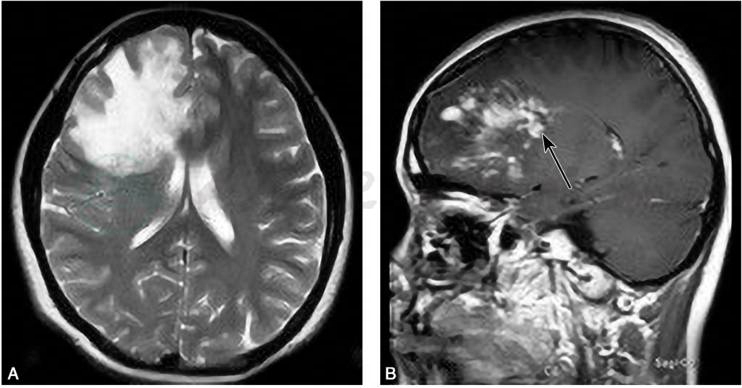

4)灌注加权成像(perfusion weighted imaging,PWI):

可用来评价病灶内的血流灌注情况,主要有两种方法:①需静脉团注外源性对比剂(如Gd-DTPA)的动态磁敏感对比增强(dynamic susceptibility contrast-enhanced,DSC)方法;②完全无创的动脉自旋标记(arterial spin labeling,ASL)方法。胶质瘤新生血管多,往往呈高灌注,而TIDD一般不出现高灌注表现(图8)。

图8灌注加权成像

病例1,女性,50岁,主因“癫痫1天”入院,胶质母细胞瘤,轴位T1WI增强示:左侧顶枕交界皮质可见结节样强化病灶(A),在 ASL像呈高灌注(B);病例2,男性,44岁,主因“意识障碍3天”入院,急性起病,TIDD,轴位DWI(C)示:双侧额叶皮质下及侧脑室旁白质可见大片融合蝶形病灶,累及胼胝体膝部,ASL显示双侧病灶处灌注无明显增高(D)

引自:神经病学:全2册.第3版.ISBN:978-7-117-31406-0.主编: